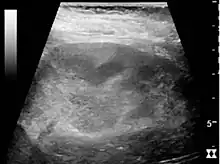

Ultrasound findings that indicate pyelonephritis are enlargement of the kidney, edema in the renal sinus or parenchyma, bleeding, loss of corticomedullary differentiation, abscess formation, or an areas of poor blood flow on doppler ultrasound.[21] However, ultrasound findings are seen in only 20–24% of people with pyelonephritis.[21]

- Abscess around both kidneys[24]